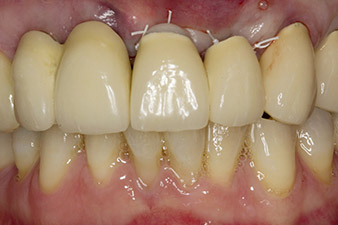

Following primary healing, the soft tissues were shaped using the basally lined bridge. Two months later the site was exposed by a slightly palatal alveolar ridge incision (Fig 2). The dimensions of the alveolar bone proved to be sufficient at position 22. Figures 2 and 4 show the preparation of the implant bed, the tapping and the implantation using Implantmed.

In this case study, the situation was resolved with an implant at position 22 in the first procedure and an additional one at the position of the extracted tooth 23 later in the course of the treatment. The second implant was inserted following successful osseointegration of implant 22. The revised bridge was reinserted until implant 23 healed in place and the shaping for the permanent restoration was complete. The advantages of this gradual approach include the implants’ being able to accept loads more resiliently and mature hard and soft tissues (5).